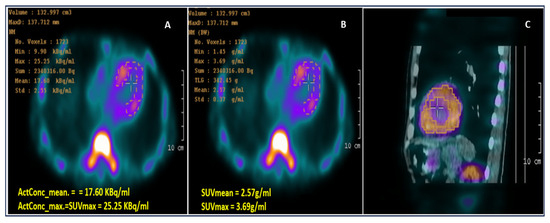

| Tc-99m PYP scintigraphy | High PPV for ATTR when grade 2–3 myocardial uptake presents with SPECT confirmation; enables noninvasive diagnosis; H/CL ratio adds confidence | False positives if only planar imaging; rare uptake in AL; requires exclusion of pathogenic monoclonal protein | Primary noninvasive discriminator: grade 2–3 uptake + negative AL work-up strongly supports ATTR |